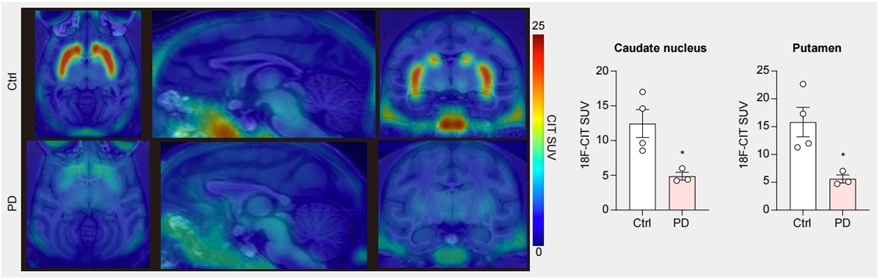

圖3. PET-CT結果顯示PD模型猴腦中多巴胺神經元減少